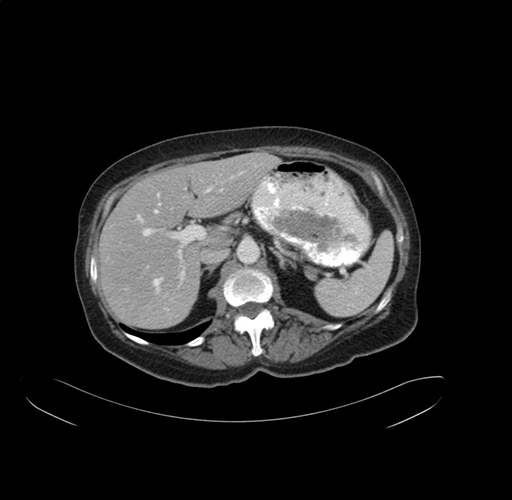

Pre-Chemo: Axial Venous

Axial Venous